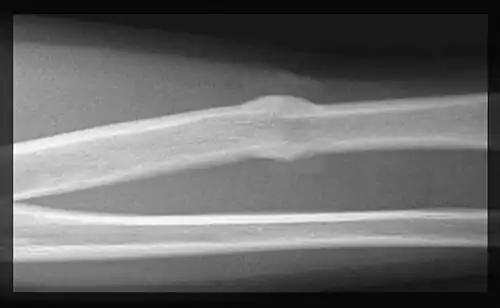

Zunächst tritt aus der Bruchfläche Blut aus und es bildet sich ein Bluterguss (Hämatom). Dies führt zu einer Aktivierung der Entzündungskaskade und Entzündungszellen setzen Zytokine wie Interleukin-1 und Interleukin-6 frei. Das Blut gerinnt, wird durch Granulationsgewebe ersetzt und es bildet sich zunächst eine bindegewebige Narbe. Diese Prozesse bilden zunächst eine elastische Verbindung der Bruchenden und schränken deren Beweglichkeit ein. Durch eingewanderte Knorpelbildner (Chondroblasten) kommt es zur Bildung von Faserknorpel, der allmählich durch aktivierte Osteoblasten verknöchert. Die so entstandene Manschette ist deutlich dicker als der übrige Knochen und wird als «Kallus» bezeichnet. Die mechanische Stabilität des Kallus ist jedoch deutlich geringer als die von intaktem Knochengewebe. Auch bei der sekundären Knochenheilung setzt nun ein Knochenumbau (remodeling) ein, und der Kallus wird nach und nach abgebaut und durch entsprechend den Trajektorien ausgerichtetes Knochengewebe ersetzt. Je nach Ausmaß der Fraktur kann die vollständige Knochenausheilung zwischen sechs und zwölf Monaten dauern.